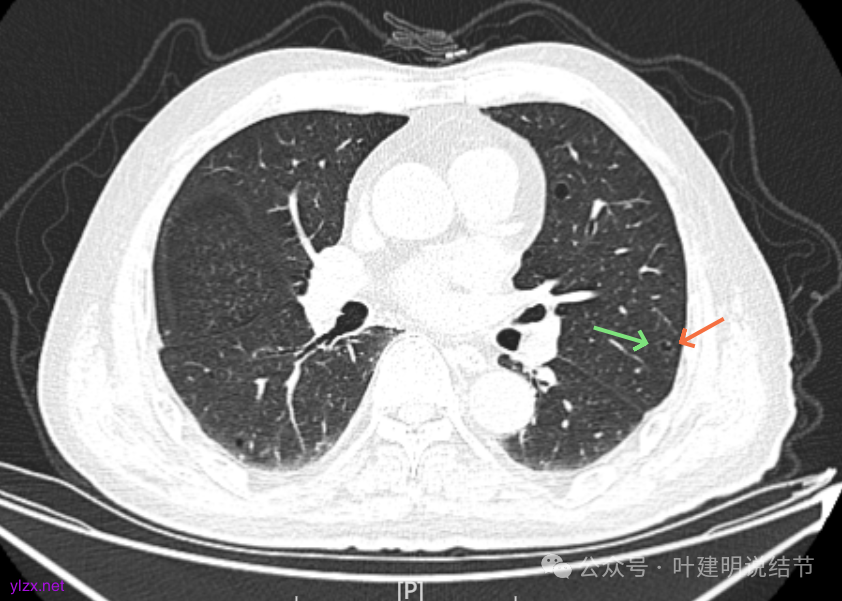

右下叶也有囊腔灶。

两肺其他地方多处肺大泡。

左肺上叶红色这处是囊腔型病灶,囊壁略不均,似有微小血管进入囊壁,对比2023年4月整个囊腔来讲有扩大,需要考虑囊腔型肺癌的可能性大。右侧蓝色的并不是典型囊腔型肺癌的表现,再加上两肺绿色这些慢支肺气肿与肺大泡的影像,右侧的就更加不确切,至少近期不能够考虑右侧也要开刀的事情。其实左侧的主病灶相对于其他表现更典型的囊腔型肺癌来说,由于囊壁密度偏高,也不是百分百必定是肺癌。我的想法还是先等脑梗情况稳定,并且间隔4~6个月复查病灶再有进展在考虑单孔胸腔镜下局部切除就可以。淋巴结可以考虑采样,但一般不至于阳性。破是不会切破的。消融不建议,囊腔灶更难通过穿刺获得病理依据,况且东西在边上,能局部楔切,当然首选手术。意见供参考!

左侧这个病灶总体上看仍是囊腔型肺癌可能性大些,但因为其两肺存在多发肺大泡的基础,而且囊壁除了结节状高密度的以外,其他的部分虽欠均匀,但差别并不太大。所以100%恶性还是难以认定的。假如没有脑梗情况,位置在边上,早点切了明确并去除病灶当然是可行的。但在反复脑梗发作的情况下,本身要神经内科情况稳定再手术较为安全,加上无法确切认定必恶性,再适当的随访也不至于影响预后。所以仍是利弊权衡与如何平衡的事情。对于这种囊腔灶,或囊肿为表现的肺癌,其实穿刺不容易阳性,针越过组织的距离并不长,其内又是空的或是液体性质的。从临床经验来看,囊腔型肺癌若囊壁是实性的,确实低分化类型的更常见些,相对风险较高些。但若是囊壁磨玻璃成分的,则也仍是贴壁为主型多见。而且从大小来讲,个人总觉得囊腔部分不能算大小,肿瘤的有形成分应该是减去空腔部分的,所以不能认定CT上测量的包括囊腔部分的来算肿瘤大小的T值。